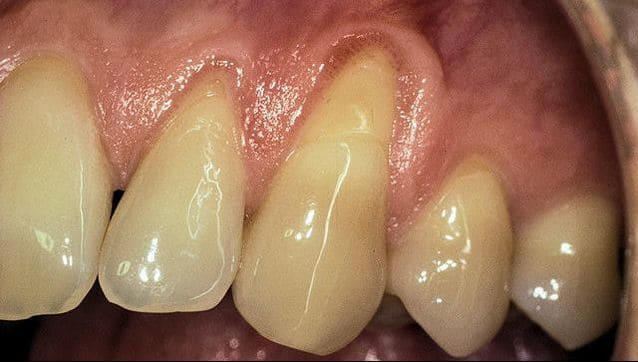

Before

Patient: Jill